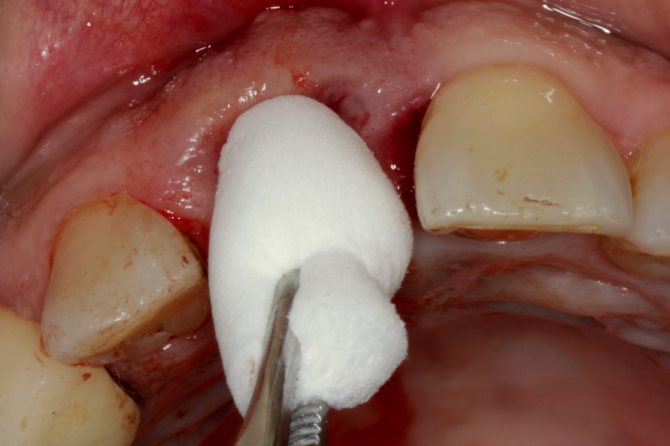

Если в десне остался осколок, нельзя затягивать с посещением врача. Специалист удалит остаточные фрагменты и обработает рану антисептиком. Операция выполняется двумя способами:

- при нахождении осколка на поверхности извлечение осуществляется за несколько минут специальным инструментом;

- если кусочек расположен глубоко, для его экстракции выполняется надрез десны.

Удаление мелких обломков

При подозрении на присутствие осколков в десне имейте в виду, что обломков может быть несколько. Стоматолог после антисептической обработки назначит рентген патологического участка, чтобы определить количество кусочков, местоположение и глубину расположения. Фрагменты, расположенные на поверхности десны, удаляются хирургическим инструментом без осложнений.

Глубоко осевшие фрагменты нуждаются в оперативном вмешательстве под местным обезболиванием. Стоматолог удаляет их после надреза десны. При необходимости проводят повторный рентген, но обычно профессиональное удаление выполняется быстро и без осложнений. Особо сложные хирургические операции выполняют под общим наркозом.